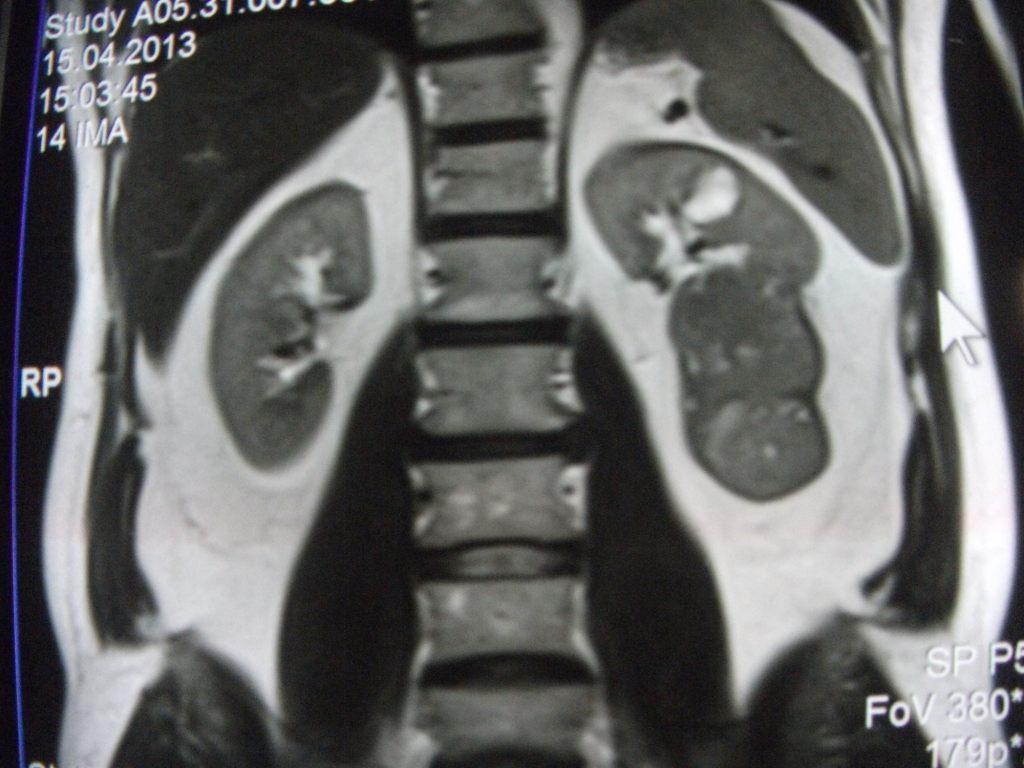

такое заключение: Левая почка: расположена обычно, увеличена, общими размерами около 13х5,5см. В области средней и нижней трети почки определяется объёмное образование неправильной формы, деформирующее наружный контур почки, распространяющиеся с чашечно-лоханочную систему. Опухоль имеет четкие неровные бугристые контуры с наличием псевдокапсулы, неоднородной структуры с признаками распада, максимальными размерами около 78,7х47х48мм